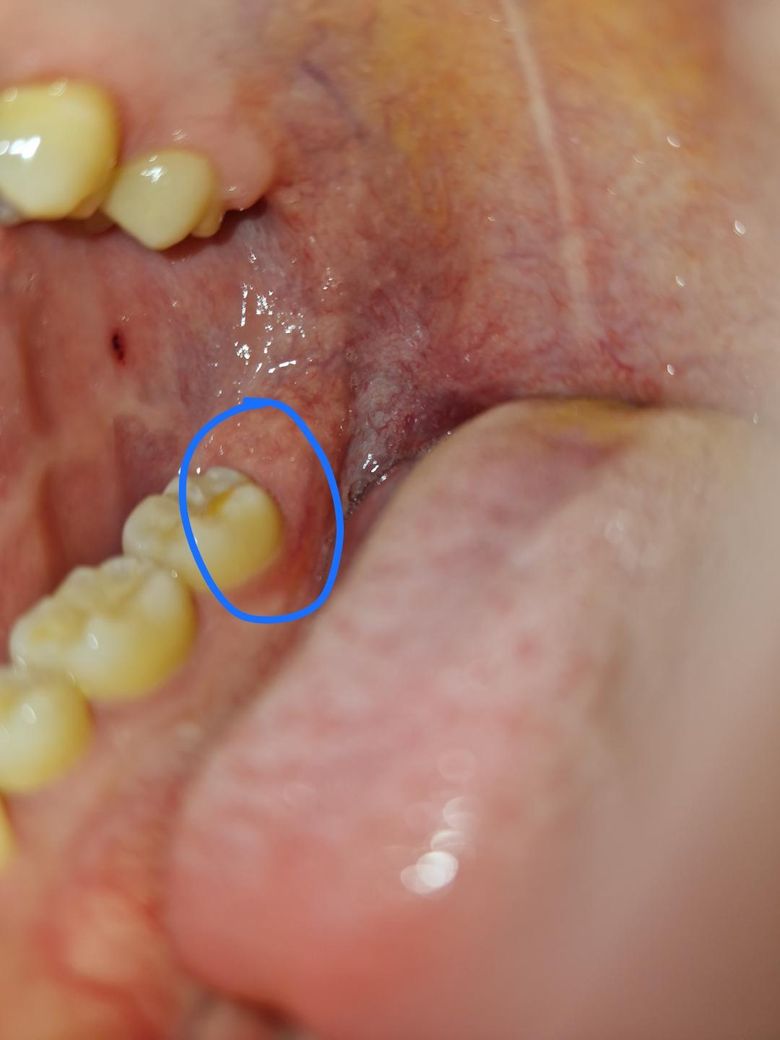

어금니 뒤쪽 잇몸이 내려간 것? 같아요

어금니 뒤 잇몸이 내려간 것 같아요. 다른 쪽 어금니에 비해 어금니 뒤쪽이 만져질 정도로요. 사랑니 때문인가요? 시간이 지나면 다시 원래대로 돌아올 수 있나요?

• 1번 째 사진